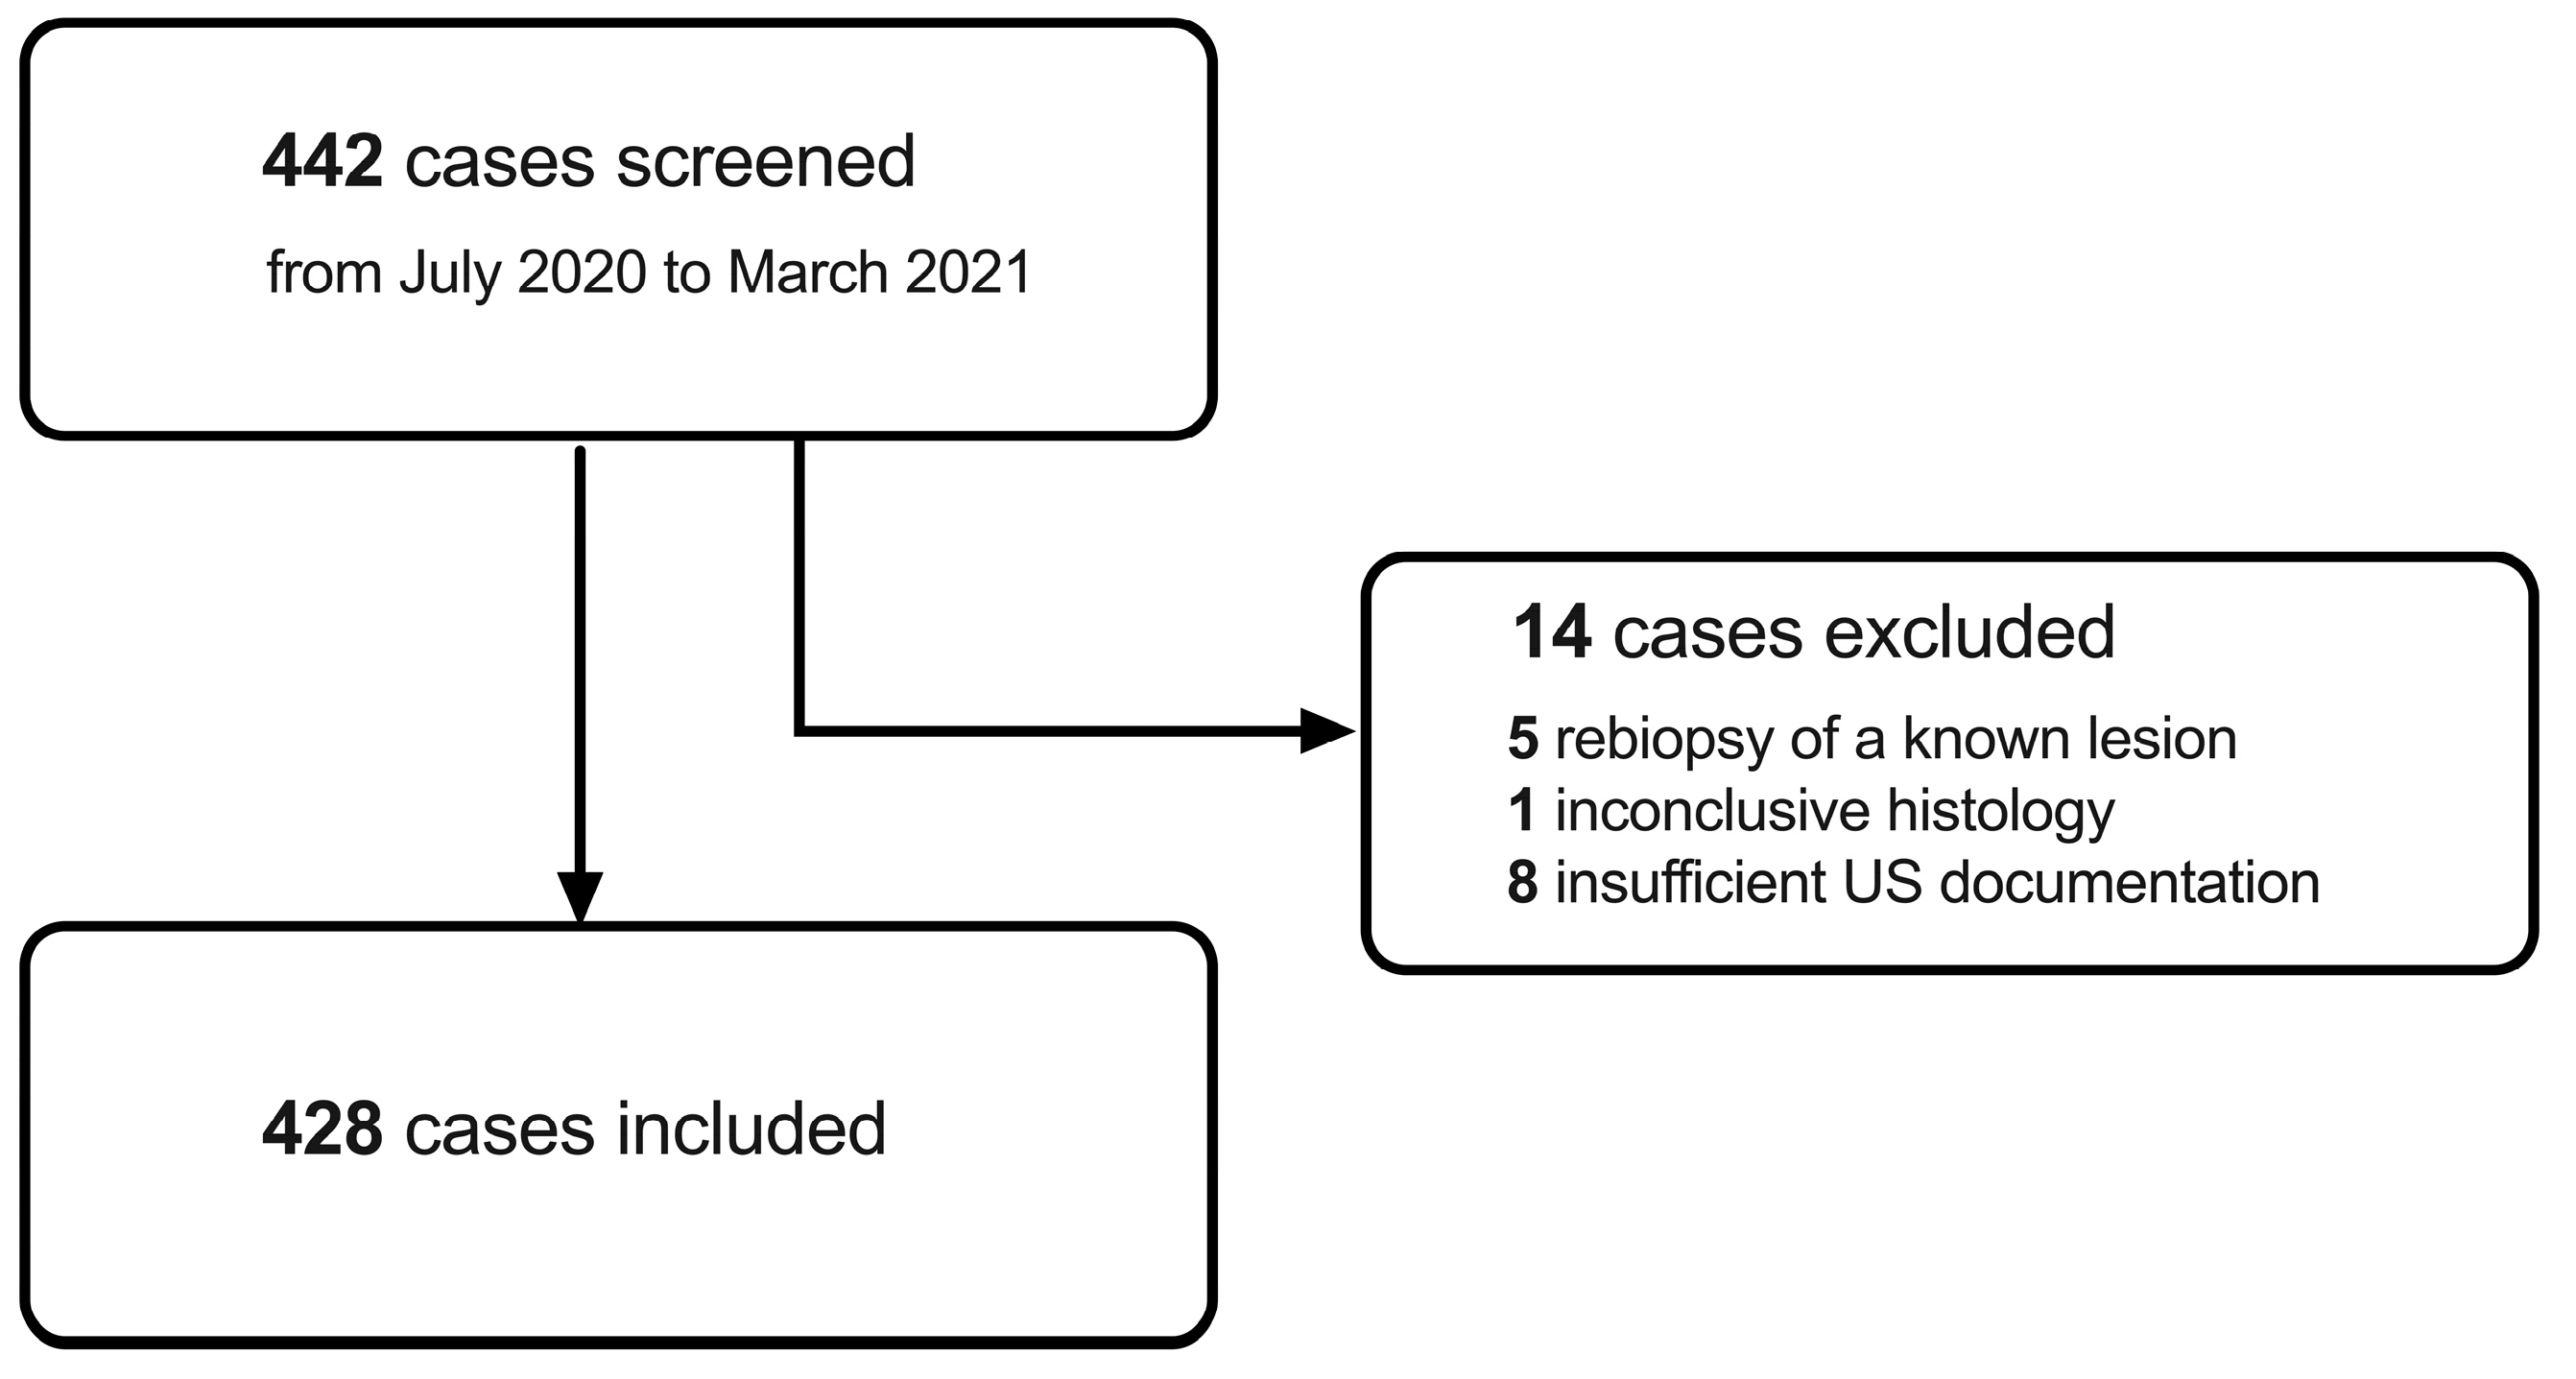

2.2. Inclusion Criteria and Screening Procedure

3.1. Patient Demographics and Lesion Characteristics